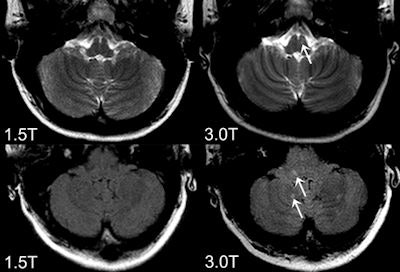

In neuroradiology, the benefits of 3-tesla are quite obvious, not only to obtain better quality routine structural imaging (e.g. of inflammatory lesions), but especially for applications with inherently low SNR, such as susceptibility weighted imaging (SWI), MR angiography (MRA), diffusion tensor imaging (DTI), functional MRI (fMRI), and MR spectroscopy. "However, still up for debate is the crucial question of the diagnostic relevance of 3-tesla MRI, or in other words, 'Does 3-tesla MRI lead to a more sensitive (earlier) and/or more specific diagnosis of certain diseases?' " the authors wrote.

"It has been conclusively shown that 3 tesla shows more (small) inflammatory white and gray matter lesions and offers a better visualization of smaller arterial branches on time-of-flight and contrast-enhanced MR angiography. Despite the fact that this might not lead to an earlier diagnosis of multiple sclerosis, or an earlier detection of aneurysm or vessel malformation with significant therapeutic consequence, (neuro)radiologists would opt for the better image quality if this came at the same cost and level of safety, because it makes the reading procedure easier and more reliable," the authors added.